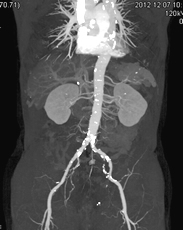

X線CT検査

X線装置を回転させることで、体内の断面像を画像として得ることができます。

造影剤という薬品を用いることで、血管や病変部を強調することもできます。

また、画像処理することにより、立体的な表示や血管部分のみを描出することもできます。

「診断部門」に320列CT装置と64列CT装置、救急外来に80列CT装置が稼働しています。